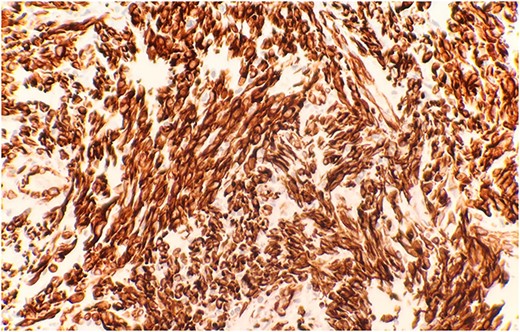

The pathological sections taken from the mass demonstrated spindle-tumor cells within a focal sclerotic and myxoid stroma with increased mitotic activity; no necrosis was visualized (Fig. 1). The vessels from the pleural mass showed a staghorn-like appearance. Tumor cells biopsied from the lung mass were positive for vimentin and CD10, as well as biomarkers for sarcomatoid mesothelioma: WT1 and D2–40 (Fig. 2). The tissue sample was negative for immunostains keratin and calretinin, which is unusual for mesothelioma. The lung mass biopsy was also negative for cytokeratin (CK) and PAX8, which ruled out the possibility of metastatic RCC. Due to the visualization of staghorn-appearing vessels, malignant solitary fibrous mesenchymal tumor was considered as well but was ruled out due to lack of STAT6 expression.

Immunohistochemical stain reveals that tumor cells are positive for WT-1 (IHC stain x40).